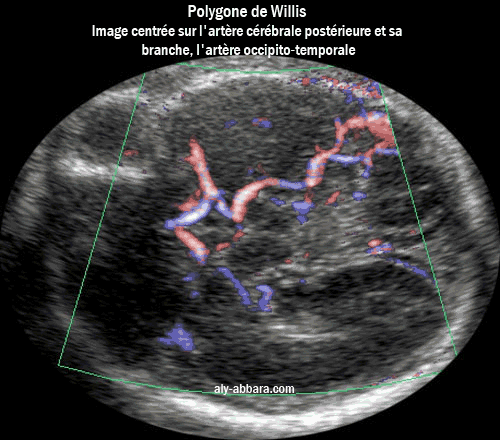

Coupe axiale (coronale) du cerveau fœtal à 26 SA

Le polygone de Willis et l'artère cérébrale postérieure avec sa branche externe,

l'artère occipito-temporale

L'artère cérébrale postérieure et sa branche occipito-temporale